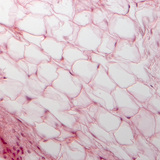

200х увеличение

Биология и здравно образование